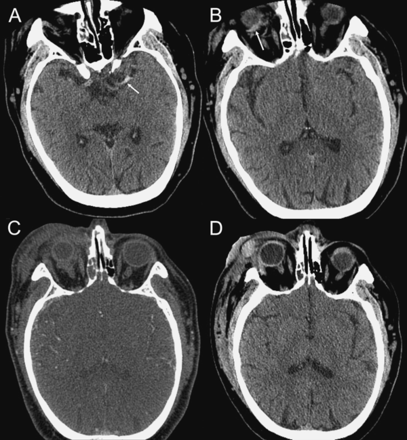

病人中有高密度的异常在左大脑中动脉近端初始41成像在急性血栓形成(图,一个)。他收到第四tPA 2小时内出现症状,并注意到重要的神经功能改善的20分钟内启动治疗。

(A)最初的头部CT在左侧大脑中动脉高密度异常(箭头所指)。(B)对retro-orbital血肿(箭头所指)。第四(C) CT血管造影术后重组组织纤溶酶原激活物管理演示retro-orbital血肿扩张,进步眶周的水肿,以及不断恶化的突出。(D)溶栓演示间隔24小时后头部CT改善retro-orbital血肿以及最小脑缺血性改变。

大约45分钟后启动第四重组tPA,病人开发增加单眼失明和完全关闭的右眼迅速进步的眶周的水肿和淤血。复审的颅骨成像表示和静脉溶栓后确认一个扩大retro-orbital血肿(图中,B和C)。紧急外眦切开术进行减压视神经,3天内轨道减压和缺血性中风的治疗,他已经接近完整的视觉和神经功能恢复。后续颅和轨道成像表现后24小时内眦切开术演示了解决retro-orbital血肿(图D)。